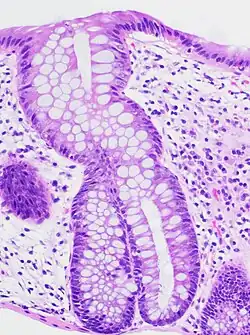

An important investigation in the assessment of colitis is biopsy for histopathology. A very small piece of tissue (usually about 2mm) is removed from the bowel mucosa during endoscopy and examined under the microscope by a histopathologist. A biopsy report generally does not state the diagnosis, but should state any presence of chronic colitis, give an indication of disease activity, as well as state the presence of any epithelial damage (erosions and ulcerations).[6]

Histopathology findings generally associated with chronic colitis include:[6]

Crypt degeneration -

Crypt branching and other architectural distortions -

Paneth cell (pictured) or gastric metaplasia (only applies in the left colon and rectum)

Other findings include basal plasmacytosis and mucin depletion.[6] Histopathology findings generally associated with active colitis include:[6]

-

Neutrophilic cryptitis (neutrophils within crypt epithelium) -

Crypt abscesses (luminal neutrophilic aggregates) -

Gland destruction -

Ulceration (seen here as absence of epithelium, and granulation tissue with many fibroblasts)